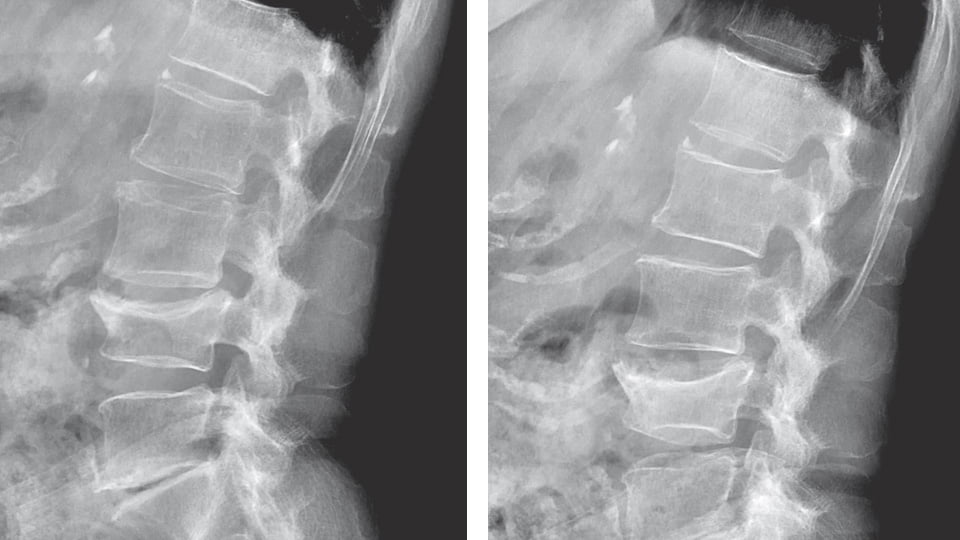

また、レントゲン検査で背骨の高さを正確に測定する必要がありますが、骨粗鬆症の背骨は曲がっていることが多く、側面1枚で正確な高さを測定することは困難です。そのため当院では透視装置を用いています。透視下で各背骨に平行にレントゲン線が入るよう調整しながら何枚も撮影を行います。その結果、全脊椎一個一個の正確な高さを数値化できます。診療報酬は、正面・背面1枚ずつしか請求できませんが、コストよりもクオリティーを追求しています。